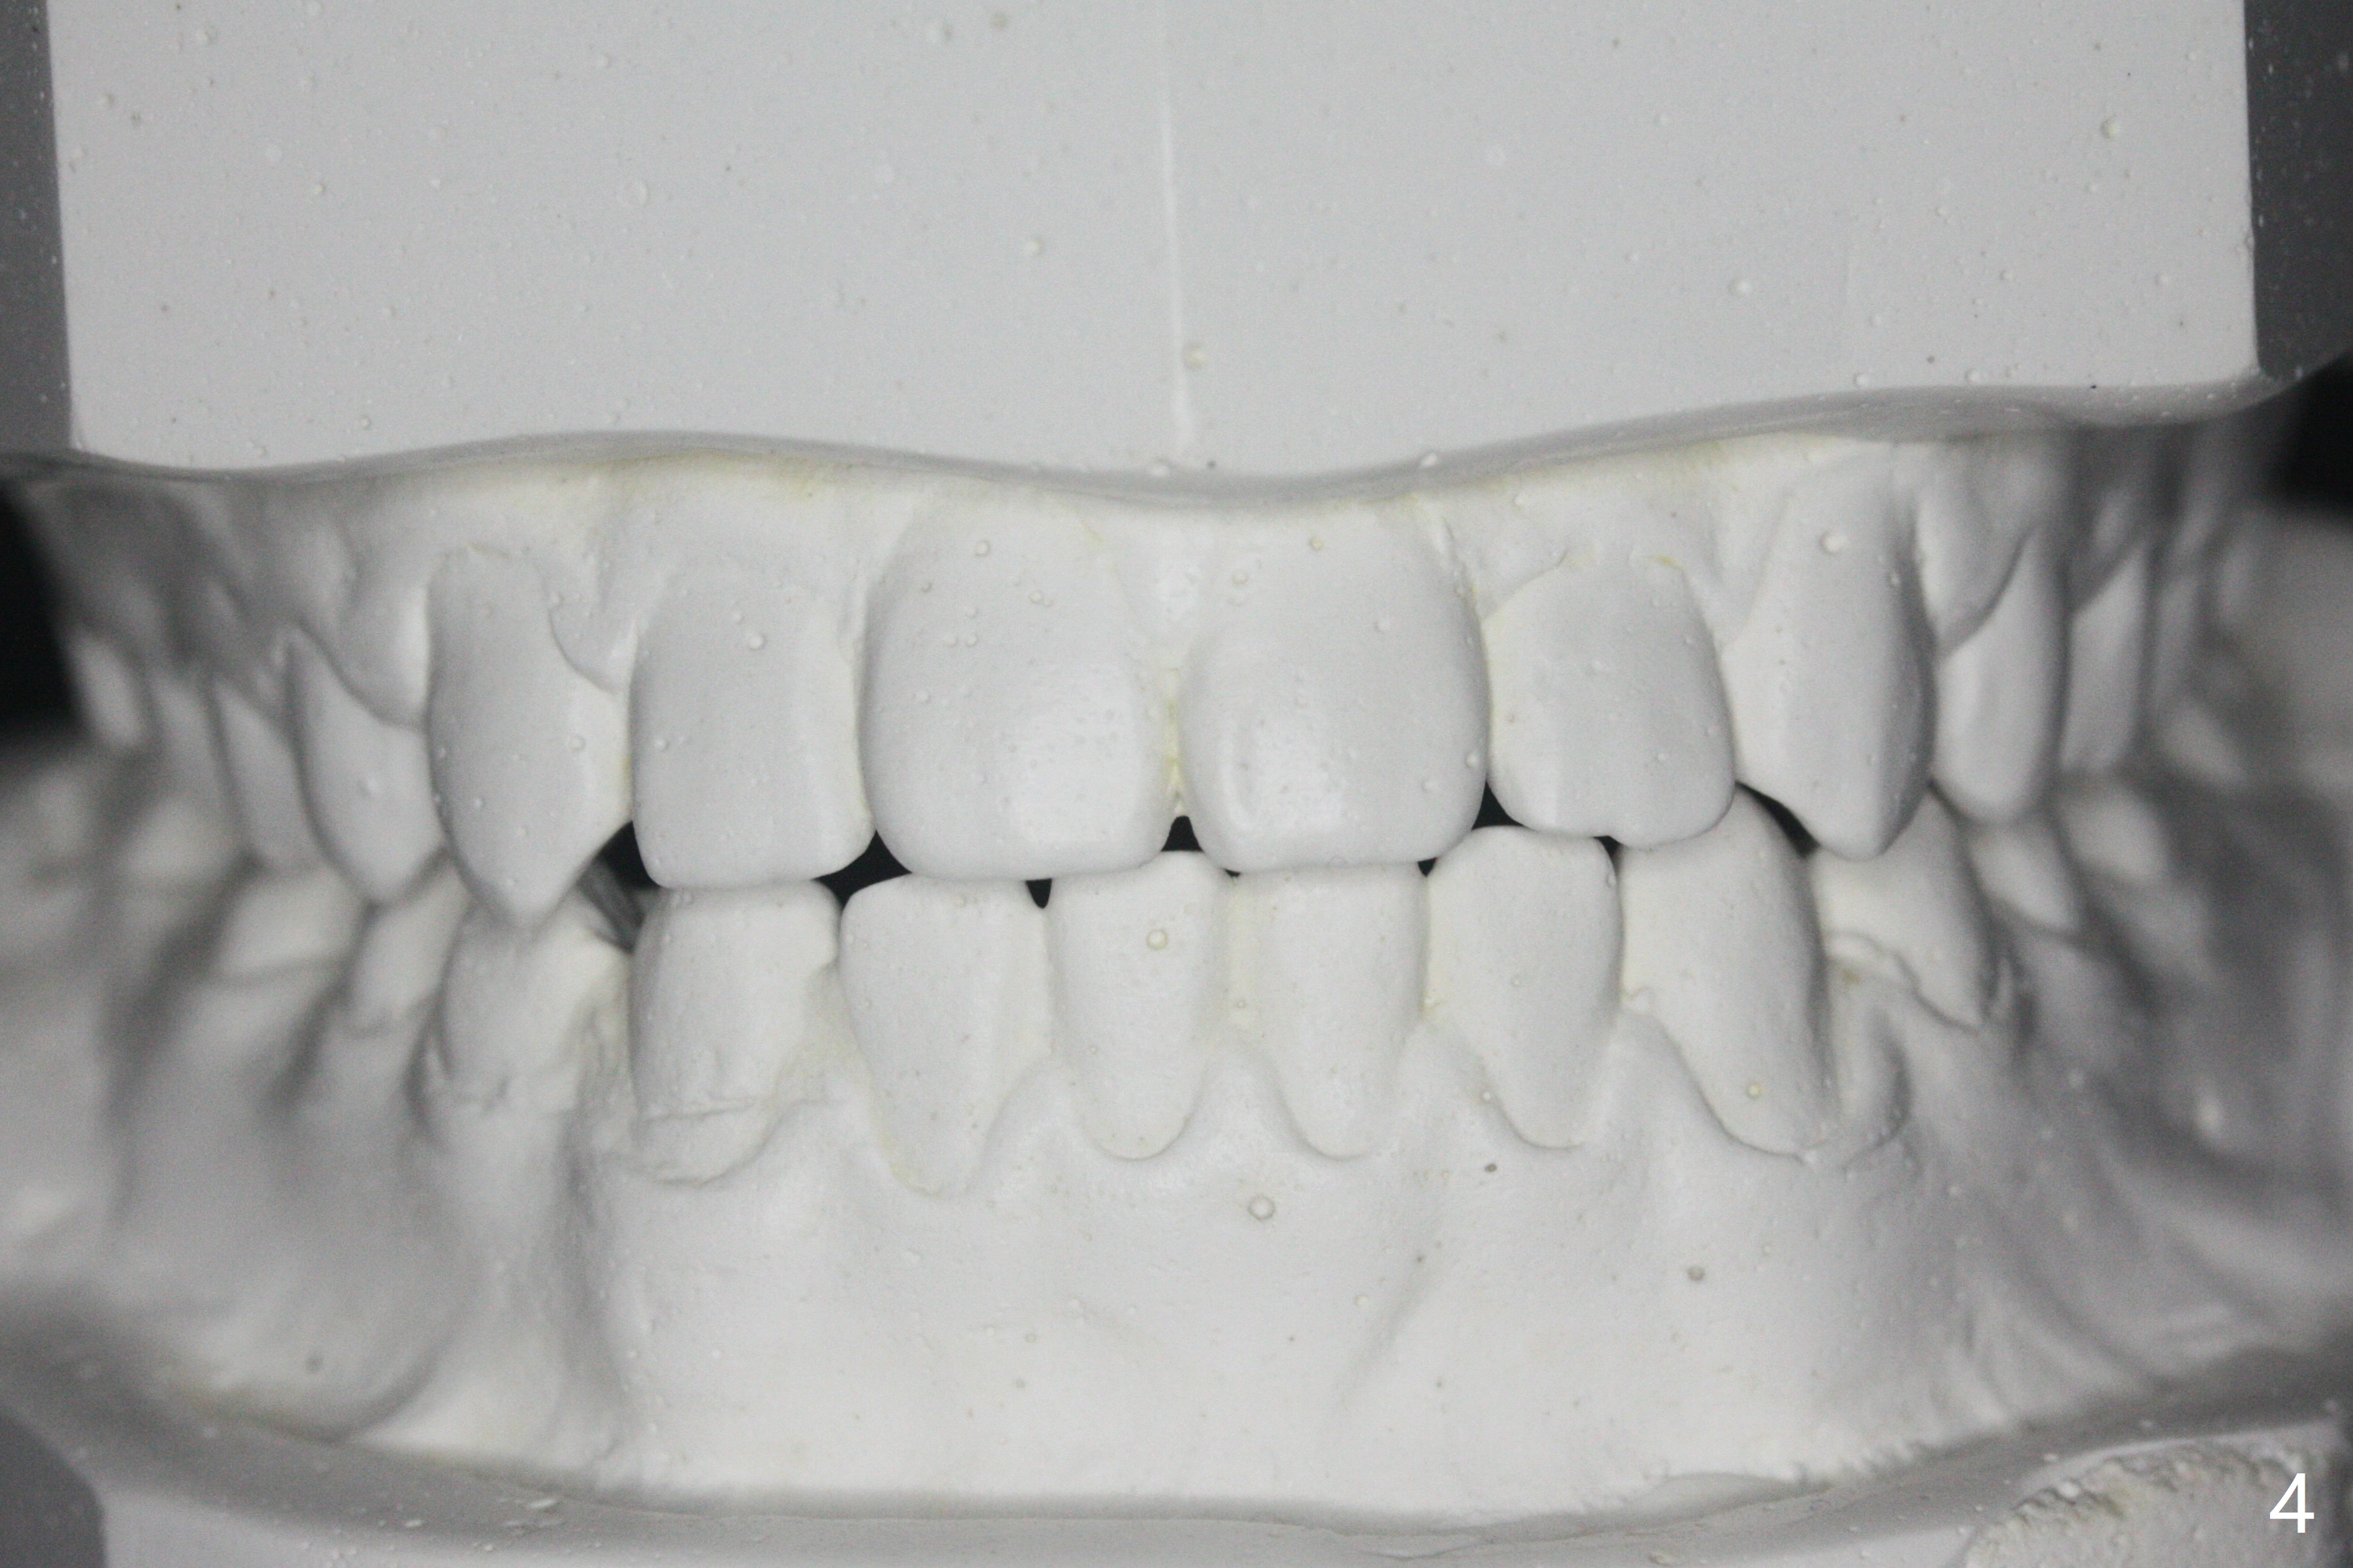

15岁男完成矫正1年9月,右侧后牙咬合理想(图二),上中切牙长轴改善,侧切牙torque不够完善(图四),左侧后牙咬合二类𬌗(图六,需要牵引),磨牙缝隙大(图八,十),造成食物堵塞,以后尽量避免使用磨牙bands,尤其是成人。